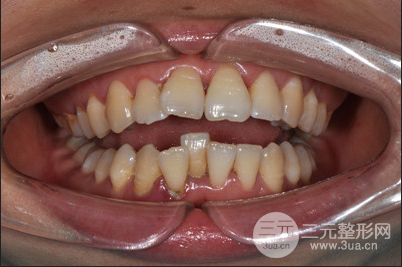

牙齒矯正時(shí)間真的太漫長了,在15年做的牙齒矯正,當(dāng)時(shí)還是找的黎主任做的面診和整個(gè)較真過程,一直以來牙齒很不整齊,關(guān)鍵是還有凸嘴的困擾,在面診之后才知道原來是上下牙列擁擠、上下頜牙弓狹窄、雙頜前突,做牙齒矯正是在所難免的了。

對(duì)一次緩解拔了四顆智齒,太專業(yè)的緩解矯正過程我也說不上來,只知道為了減輕牙齒之間的擁擠程度,不得不拔牙,其實(shí)我的凸嘴不算特別嚴(yán)重,在拔牙之后做矯正固定就可以了,但是既然選擇了做整形就要做到很好的果,所以在醫(yī)生的專業(yè)保障下做了牙齒正畸,開始了我的漫長牙套之路。

矯正期間沒個(gè)一段時(shí)間就要回醫(yī)院做復(fù)查和更換牙套,好在醫(yī)生的技術(shù)比較好,牙齒矯正比較爭氣,現(xiàn)在想過很滿意,不僅沒有凸嘴,牙齒也很整齊,現(xiàn)在已經(jīng)取了牙套之后可以隨意吃吃喝喝了,這兩天沒有白堅(jiān)持。